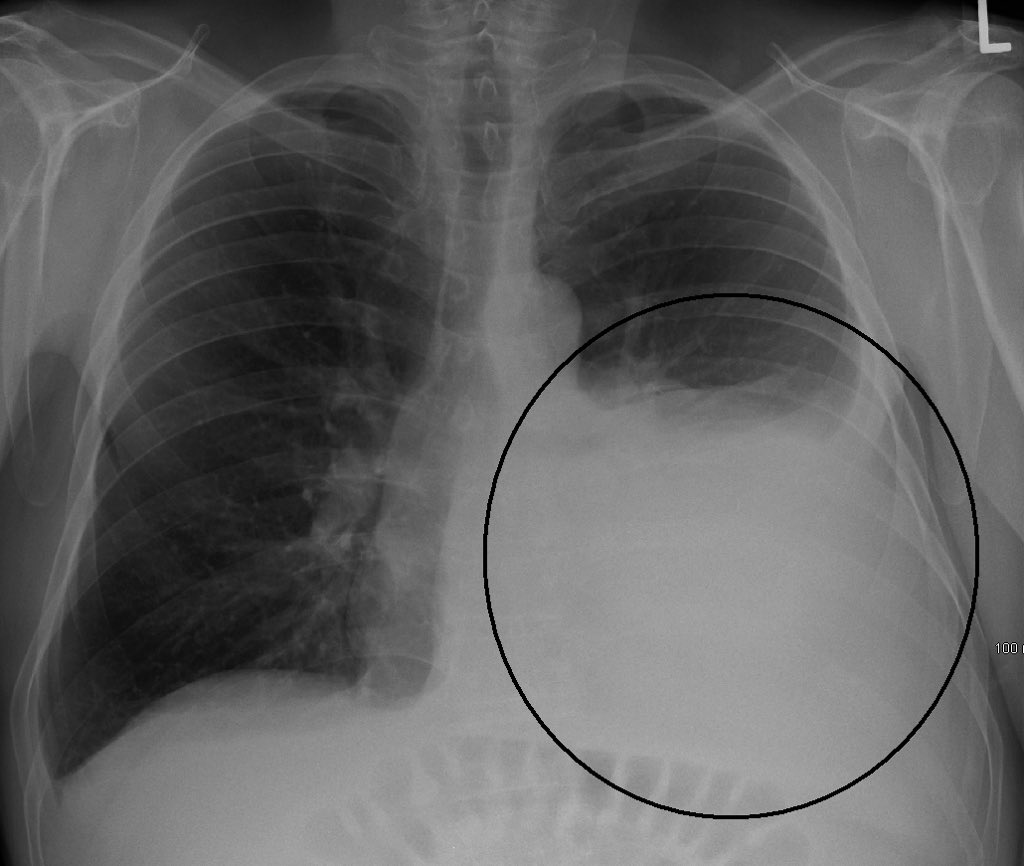

Khairul Hafidz On Twitter Boleh Lihat Gambar Utk Paru Berair Paru Berair Adalah Komplikasi Patologi Bukan Krn Mandi Mlm Perangmelawanmitos Https T Co Kjrijmkxqd